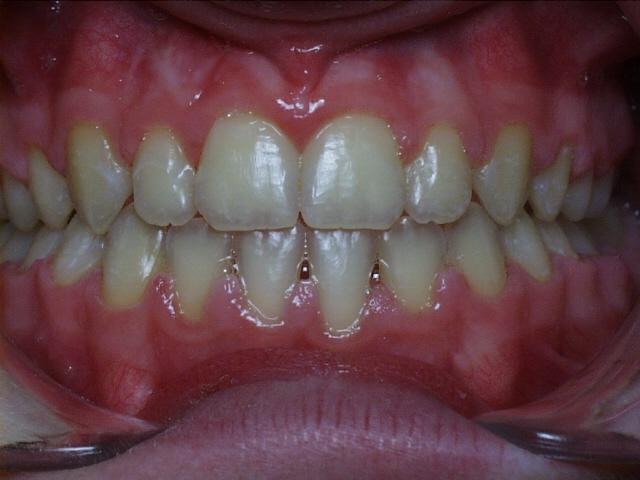

Severe overbite with mild upper and lower crowding.  Treatment time was 29 months.  No permanent teeth were extracted in this case.  The molars were class 2 (upper molars too far forward at start of treatment).  This patient can have bonding performed by his general dentist to repair the chipped front tooth.